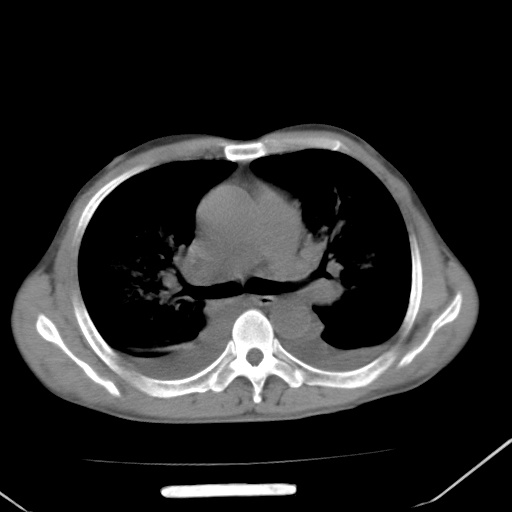

男、42岁、咯血3天。既往有甲亢、贫血、血尿蛋白尿史多年。血象:wbc:6.   中性粒:70.6%。

结合病史考虑双肺泡积血,双侧胸腔少量积液;肺水肿待排(肺水肿症状重)。

双肺堆成磨玻璃影,双测胸腔积液。考虑:肺水肿、间质性肺炎、真菌感染、ards、hiv感染、肺出血。

双肺野对称性磨玻璃影,分布于内中带,双侧胸水,患者有咯血。

双肺野广泛对称性磨玻璃影、实变影,以肺门为中心,主要分布于内中带,符合典型肺泡性肺水肿;伴双侧胸腔少量游离积液。结合患者既往病史且咯血就诊,支持多因素(尿毒症等)所致之肺水肿、肺出血、胸水;影像表现暂不考虑心源性水肿,且症状也不太符。需密切随诊结合临床治疗等进一步明确。

心影增大密度略低,双肺磨玻璃样高密度影及双侧胸腔积液,考虑心功能不全继发双肺肺水肿及双侧胸腔积液。心影密度略低,考虑贫血所致。